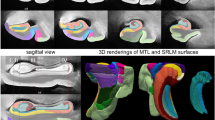

A growing number of studies have used in vivo structural MRI to derive measurements of subtle volumetric changes in the MTL caused by neurodegeneration [11, 24]. Most recently, Wisse et al. conducted a postmortem study which investigated the association between the thickness of MTL subregions in ex vivo MRI and semi-quantitative ratings of different neurodegenerative pathologies derived from histology samples taken from the contralateral hemisphere [ Brain hemispheres were obtained from twenty-nine donors; one specimen from the brain bank operated by the National Disease Research Interchange (NDRI), sixteen specimens from autopsies performed at the University of Pennsylvania Center for Neurodegenerative Disease Research (CNDR) and twelve specimens from the University of Castilla-La Mancha (UCLM) Human Neuroanatomy Laboratory (HNL) in Spain. Human brain specimens were obtained in accordance with the University of Pennsylvania Institutional Review Board guidelines, and the Ethical Committee of UCLM. Where possible, pre-consent during life and, in all cases, next-of-kin consent at death was given. CNDR hemispheres were fixed in 10% formalin solution for at least 30 days before extracting intact MTL blocks. HNL cases were fixed by perfusion with 4% paraformaldehyde through both carotid arteries. The blocks were then imaged on a Varian 9.4 T animal scanner at a 200 × 200 × 200 µm3 resolution. Details of the imaging protocol are provided in Additional file 1: Section 1.1 and Additional file 1: Fig. S7. Following MRI scanning, each of the specimens underwent histological processing for neuropathological examination and neuroanatomical analysis. In twenty-seven specimens, dense serial histology was performed. The specimens were cut into 2 cm blocks using custom molds that were 3D printed to fit each MTL specimen, cryoprotected and sectioned at 50 μm intervals in a sliding microtome coupled to a freezing unit (Microm, Heidelberg). For neuropathological diagnosis, we were interested in examining the anterior ERC at the mid-level of the amygdala, and the dentate gyrus (DG) and CA subfields at the mid-level of the body of the hippocampus. Therefore, for the remaining two specimens that did not undergo serial histology, two tissue blocks were cut at the level of the amygdala and hippocampal body, cryoprotected and sectioned into 50 μm sections. For each of the specimens, two adjacent sections were sampled at the mid-level of the amygdala and the hippocampal body for immunohistochemistry. In each case, the two sections were immunostained for tau and TDP-43 using anti-human PHF-Tau (monoclonal antibody (mAb), mouse, Thermo Scientific, Product Number MN1020, 1:500) and 66318-1-Ig Anti-phospho (409/410) TDP-43 (mAb, mouse, Proteintech, 1:350) respectively. Sections were then mounted on 7.5 cm × 5 cm slides and digitally scanned at 20× resolution. Regional thickness analysis was performed using histopathology ratings of tau and TDP-43 pathologies derived from the MTL both ipsilateral and contralateral to the one that was scanned. Semi-quantitative ratings for tau and TDP-43 pathology were obtained for the contralateral hemisphere by obtaining tissue samples at the time of autopsy and are available for a subset of twenty-eight donors (CNDR and HNL specimens) in three MTL regions routinely examined in the CNDR neuropathology evaluations [29]. For each of the specimens, the boundaries between MTL subregions cornu ammonis (CA) 1, CA2, CA3, DG, SUB, presubiculum, parasubiculum, hippocampal amygdala transition area (HATA), SRLM, ERC, BA35, BA36, area TE and the parahippocampal cortex (areas TF and TH) were identified on the basis of cytoarchitectural features in the Nissl stained sections following the anatomical rules presented in the Atlas of the Human Brain by Mai et al. [30]. Annotations were performed on each histology slice by the team of neuroanatomists at UCLM (the hippocampal subfields and ERC were annotated by M.M.A, E.A.P, M.M.R, M.M.L, C.R.P, S.C.S, J.C.D, M.C.P and F.M.R., supervised by R.In; R.In annotated the boundaries of the temporopolar cortex, PRC and PHC, and revised the annotations of the group). The neuroanatomists viewed scanned Nissl slides in an open-source web-based system (https://github.com/pyushkevich/histoannot) and used line drawings and text labels to annotate boundaries between adjacent anatomical regions. Following histology reconstruction and registration to MRI, the boundary annotations were overlaid on the co-registered MRI and histology images. Additionally, the manual segmentations of the whole MTL cortex and SRLM that were used to guide groupwise registration were registered to the histology images to inform the outer MTL boundary. The MRI, histology and MTL segmentation images were displayed side-by-side in ITK-SNAP [31] to facilitate manual tracing of the subfield segmentations in 3D MRI space, which was performed by S.L. with supervision from L.E.M.W and R.In (Additional file 1: Fig. S9). For each of the eleven specimens, the completed segmentations were then mapped to the MRI atlas using the deformable transformations generated by the groupwise registration pipeline. Note that for each specimen, small gaps in the segmentation may exist between blocks. A consensus segmentation of the MRI atlas was obtained by application of voxel-wise majority voting among the eleven segmentations with slight regularization by a Markov Random Field prior. More details on this approach are provided in the supplemental information, Section S1.4.5 of Adler et al. [1: Section 1.4). To test the effects of tau pathology on regional thickness, we fit a general linear model (GLM) at each vertex on both the MTL and SRLM surfaces with the average rating of tau pathology as the independent variable, thickness as the dependent variable, and age and TDP-43 rating as covariates. More details on the statistical analysis are provided in Additional file 1: Section 1.5. The specimens included in this study contain varying neuropathological diagnoses, including AD neuropathologic change and neuropathological diagnoses such as argyrophilic grain disease (AGD), frontotemporal lobar degeneration (FTLD) with TDP-43 inclusions, cerebrovascular disease and Lewy body disease. Figure 1 summarizes the demographic and neuropathology data for this brain donor cohort. The average ipsilateral tau and TDP-43 ratings across the twenty-nine specimens are 1.50 ± 0.97 and 0.54 ± 0.82 respectively. The average age is 74 years (range 44–93 years). Additional file 1: Table S2 provides more detailed demographic data and pathology information for each specimen. Demographic and diagnostic summaries for the twenty-nine brain donors. The tau and TDP-43 pathology ratings refer to the average rating computed from measurements sampled at three medial temporal lobe locations (entorhinal cortex at the mid-level of the amygdala and subiculum/cornu ammonis and dentate gyrus at the mid-level of the hippocampus). Dashed lines are used to indicate the mean value across specimens Figure 2 shows the MRI atlas of the MTL constructed from twenty-nine ex vivo specimens as a synthetic “average” MR image and a consensus MTL subregion segmentation derived from serial histology in eleven specimens. The atlas construction pipeline achieves excellent groupwise alignment between ex vivo MRI scans and captures the average shape of the MTL (Additional file 1: Section 2.1, Additional file 1: Fig. S2, Additional file 1: Fig. S3 and Additional file 1: Fig. S4). Following groupwise registration, each specimen has a pointwise spatial correspondence to this atlas. This correspondence is limited to the region of the MTL cortex which was semi-automatically segmented in each specimen. Figure 3 provides a visualization of the quality of the registration between individual specimen images and the final atlas. In some specimens, the PRC, which includes BA35, was particularly challenging to register due to significant anatomical variability in cortical folding and branching patterns [32, 33]. Overall, the warped specimens look similar to each other following registration, although some minor mis-registrations remain. Quantitative and visual evaluation of atlas quality at different stages of atlas construction, and comparisons with an alternative atlas-building strategy are presented in Additional file 1: Section 2.1. Computational atlas of the medial temporal lobe (MTL) constructed by groupwise registration of the magnetic resonance image (MRI) scans of twenty-nine ex vivo specimens. Three coronal sections are shown ordered from anterior (ant) to posterior (post), indicated as I, II and III, as well as a sagittal and axial section through the MTL. For each section, the “average” MRI is shown with and without the consensus MTL subregion segmentation derived from serial histology in eleven specimens. In the top right, a 3D reconstruction of the MTL atlas is shown along with a 3D brain rendering indicating the location of the MTL within the brain. (med medial, lat lateral, sup superior, inf inferior, SUB subiculum, SRLM stratum radiatum lacunosum moleculare, CA cornu ammonis, DG dentate gyrus, HATA hippocampal amygdala transition area, ERC entorhinal cortex, BA Brodmann Area) Coronal view of the MRI scans of each of the twenty-nine specimens warped into the space of the MRI atlas. The corresponding atlas image is outlined in blue, in the bottom-right corner. The more similar the warped images are, the better the atlas quality. The dashed blue circles point out examples where the perirhinal cortex (region surrounding the collateral sulcus) was particularly challenging to register due to significant variability in cortical folding patterns. The color bar at the bottom of each image indicates the average neurofibrillary tangle (NFT) rating for that specimen. Yellow represents a rating of 0 (no/rare pathology) and red represents a rating of 3 (severe Alzheimer’s disease) Figure 4 shows the results of the pointwise thickness analysis performed on the MTL and SRLM examining the regional effects of tau pathology on cortical thickness using pathology ratings derived from the MTL ipsilateral to the thickness measures. Cases CNDR12 (44 y.o.) and HNL01 (45 y.o.) were excluded from the thickness analyses since these younger cases are outliers in terms of age and including them skews age effects, thereby dampening the associations between pathology and thickness. In this work we only consider the effects of tau and TDP-43 pathology on MTL structure since recent work studying the contribution of mixed pathology to MTL atrophy in AD showed no clear relationship between neurodegeneration and either Aβ or \(\alpha\)-synuclein [34, 9, 29]. These NFT density maps are generated using a weakly supervised deep learning algorithm, trained to specifically detect tangles and pre-tangles on AT8-stained sections and have been shown to correlate strongly with manual NFT counts [29]. Three cases with a primary FTLD-Tau or AGD diagnosis (CNDR01, CNDR06 and CNDR07) were excluded from the analysis since they likely contain 4R-tau inclusions which can be difficult to distinguish from AD-related NFTs. In the remaining twelve cases, we examined the correlation between the average NFT burden computed within each hotspot and the median thickness of each hotspot, and observe very strong correlations, although the hotspot in the ERC does not reach significance (Additional file 1: Fig. S12). These results are weakened when we include age in the model. This is likely due to the small sample size and the fact that age and tau are significantly correlated (average R = 0.61 across the three hotspots). Despite the small dataset, these results are encouraging and suggest that NFTs are indeed playing a role in driving neurodegeneration in the ERC, SUB and SRLM hotspots. As we expand our dataset, collect more quantitative histology data and develop automated methods to extract quantitative measures of the different types of tau and TDP-43 pathology, in future work we will be able to better overcome the above-mentioned limitations and validate the relationship between NFTs and thickness. Overall, our findings provide a more refined understanding of how tau pathology is associated with cortical thinning within the MTL and motivate further characterization of the MTL in AD using detailed ex vivo MRI analysis. The clusters identified from the tau thickness analyses indicate granular MTL regions where in vivo measures of neurodegeneration are expected to be strongly associated with tau pathology. In an exploratory analysis, we attempted to use the ex vivo derived, AD-specific hotspots (Fig. 4B) as biomarkers in a longitudinal analysis of ADNI data (not shown). While the hotspots did not show statistical effects in a group comparison of Aβ negative, tau negative (A−T−) and Aβ positive, tau positive (A+T+) patient groups with mild cognitive impairment, BA35 achieved the strongest group discrimination. The lack of statistically significant group differences with the hotspots may be due to the small ex vivo sample size, clinical heterogeneity in our dataset and difficulties in accurately aligning BA35 in the atlas. Constructing a probabilistic atlas of the MTL has far-reaching applications in AD research beyond the work shown here. Perhaps future analyses leveraging this technology in a patient cohort more consistent with the one we would expect to encounter in an AD clinical trial would result in hotspots that are more sensitive to longitudinal change in the presence of NFT pathology, potentially enabling the development of neurodegeneration biomarkers which are more effective during early AD clinical trials. Furthermore, in future work, 3D quantitative maps of NFT density derived from serial histology imaging will be mapped into ex vivo atlas space to generate a comprehensive probabilistic description of the progression of NFT pathology at each Braak stage [29, 48, 49]. This will allow us to describe NFT topography during the different stages of AD in more detail than current descriptions, which are in 2D and based on selective sampling of the MTL [1, 2]. Additionally, in a future version of the atlas, cytoarchitecture-guided anatomical labels of MTL subregions will be included from a larger number of specimens. Such an atlas would reflect anatomical ground truth and can be used to inform in vivo MRI protocols for segmentation of MTL subregions, thereby improving the accuracy of MRI biomarkers derived from these subregions.Methods